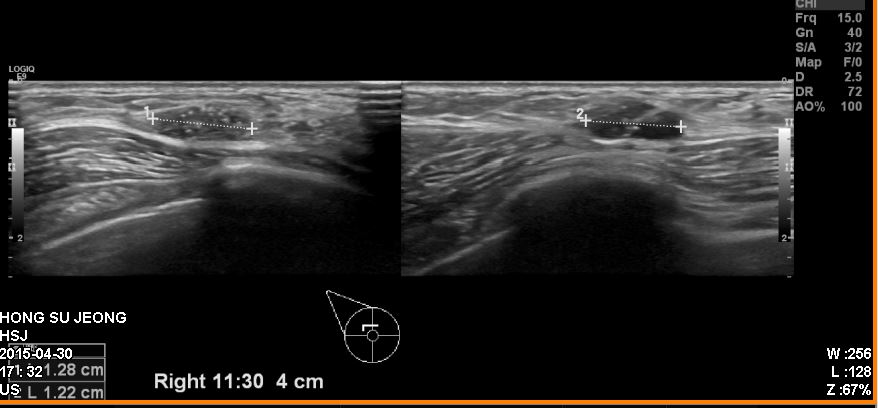

건강 검진상 이상 소견으로 내원하신 60대 여성분으로 우측 침윤성 유관암

진단 되었습니다.